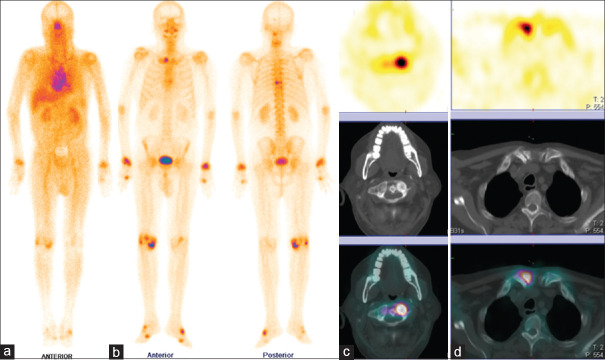

Uomo di 72 anni con artrite reumatoide sieropositiva (in terapia biologica) e dolore cervicale. Un iniziale reperto RM aveva posto il sospetto di un’infezione a livello dell’articolazione atlanto-assiale. Il paziente è stato sottoposto a scintigrafia ossea trifasica con 99mTc-MDP.

L’immagine whole-body di blood-pool (a) ha mostrato un aumentato accumulo del tracciante in entrambe le articolazioni delle spalle, nell’articolazione sternoclaveare destra, in entrambi i polsi, nel ginocchio destro e nelle piccole articolazioni di mani e piedi. L’immagine whole-body tardiva (b) ha evidenziato un’aumentata concentrazione del tracciante nelle medesime regioni che mostravano un aumentato accumulo ematico. La SPECT-TC della regione testa-collo ha mostrato un’aumentata captazione del tracciante lungo le faccette di sinistra tra le vertebre C1 e C2 (c) e nell’articolazione sternoclaveare destra (d), quadri interamente riconducibili ad artrite reumatoide attiva.